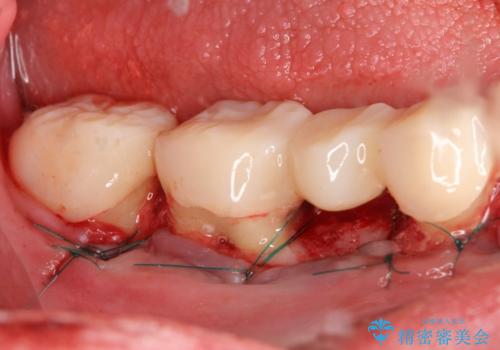

また、虫歯が歯肉の中まである場合はAPF(歯肉弁根尖側移動術)も行なっています。

適合の良い被せ物、インプラントが入りました。